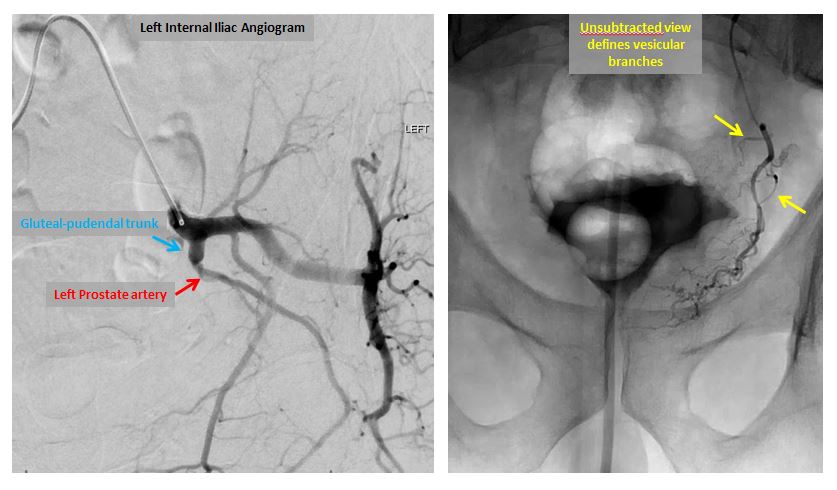

72 yo w/acute urinary retention 2/2 BPH. Remote h/o TURP. VIR consulted for PAE. Great clinical result. For more case info check out AlbanyIR.com/pae-case-1 and AlbanyIR.com/prostate-arter… for more about PAE. #IRad #PAE @SIRRFS @JVIRmedia